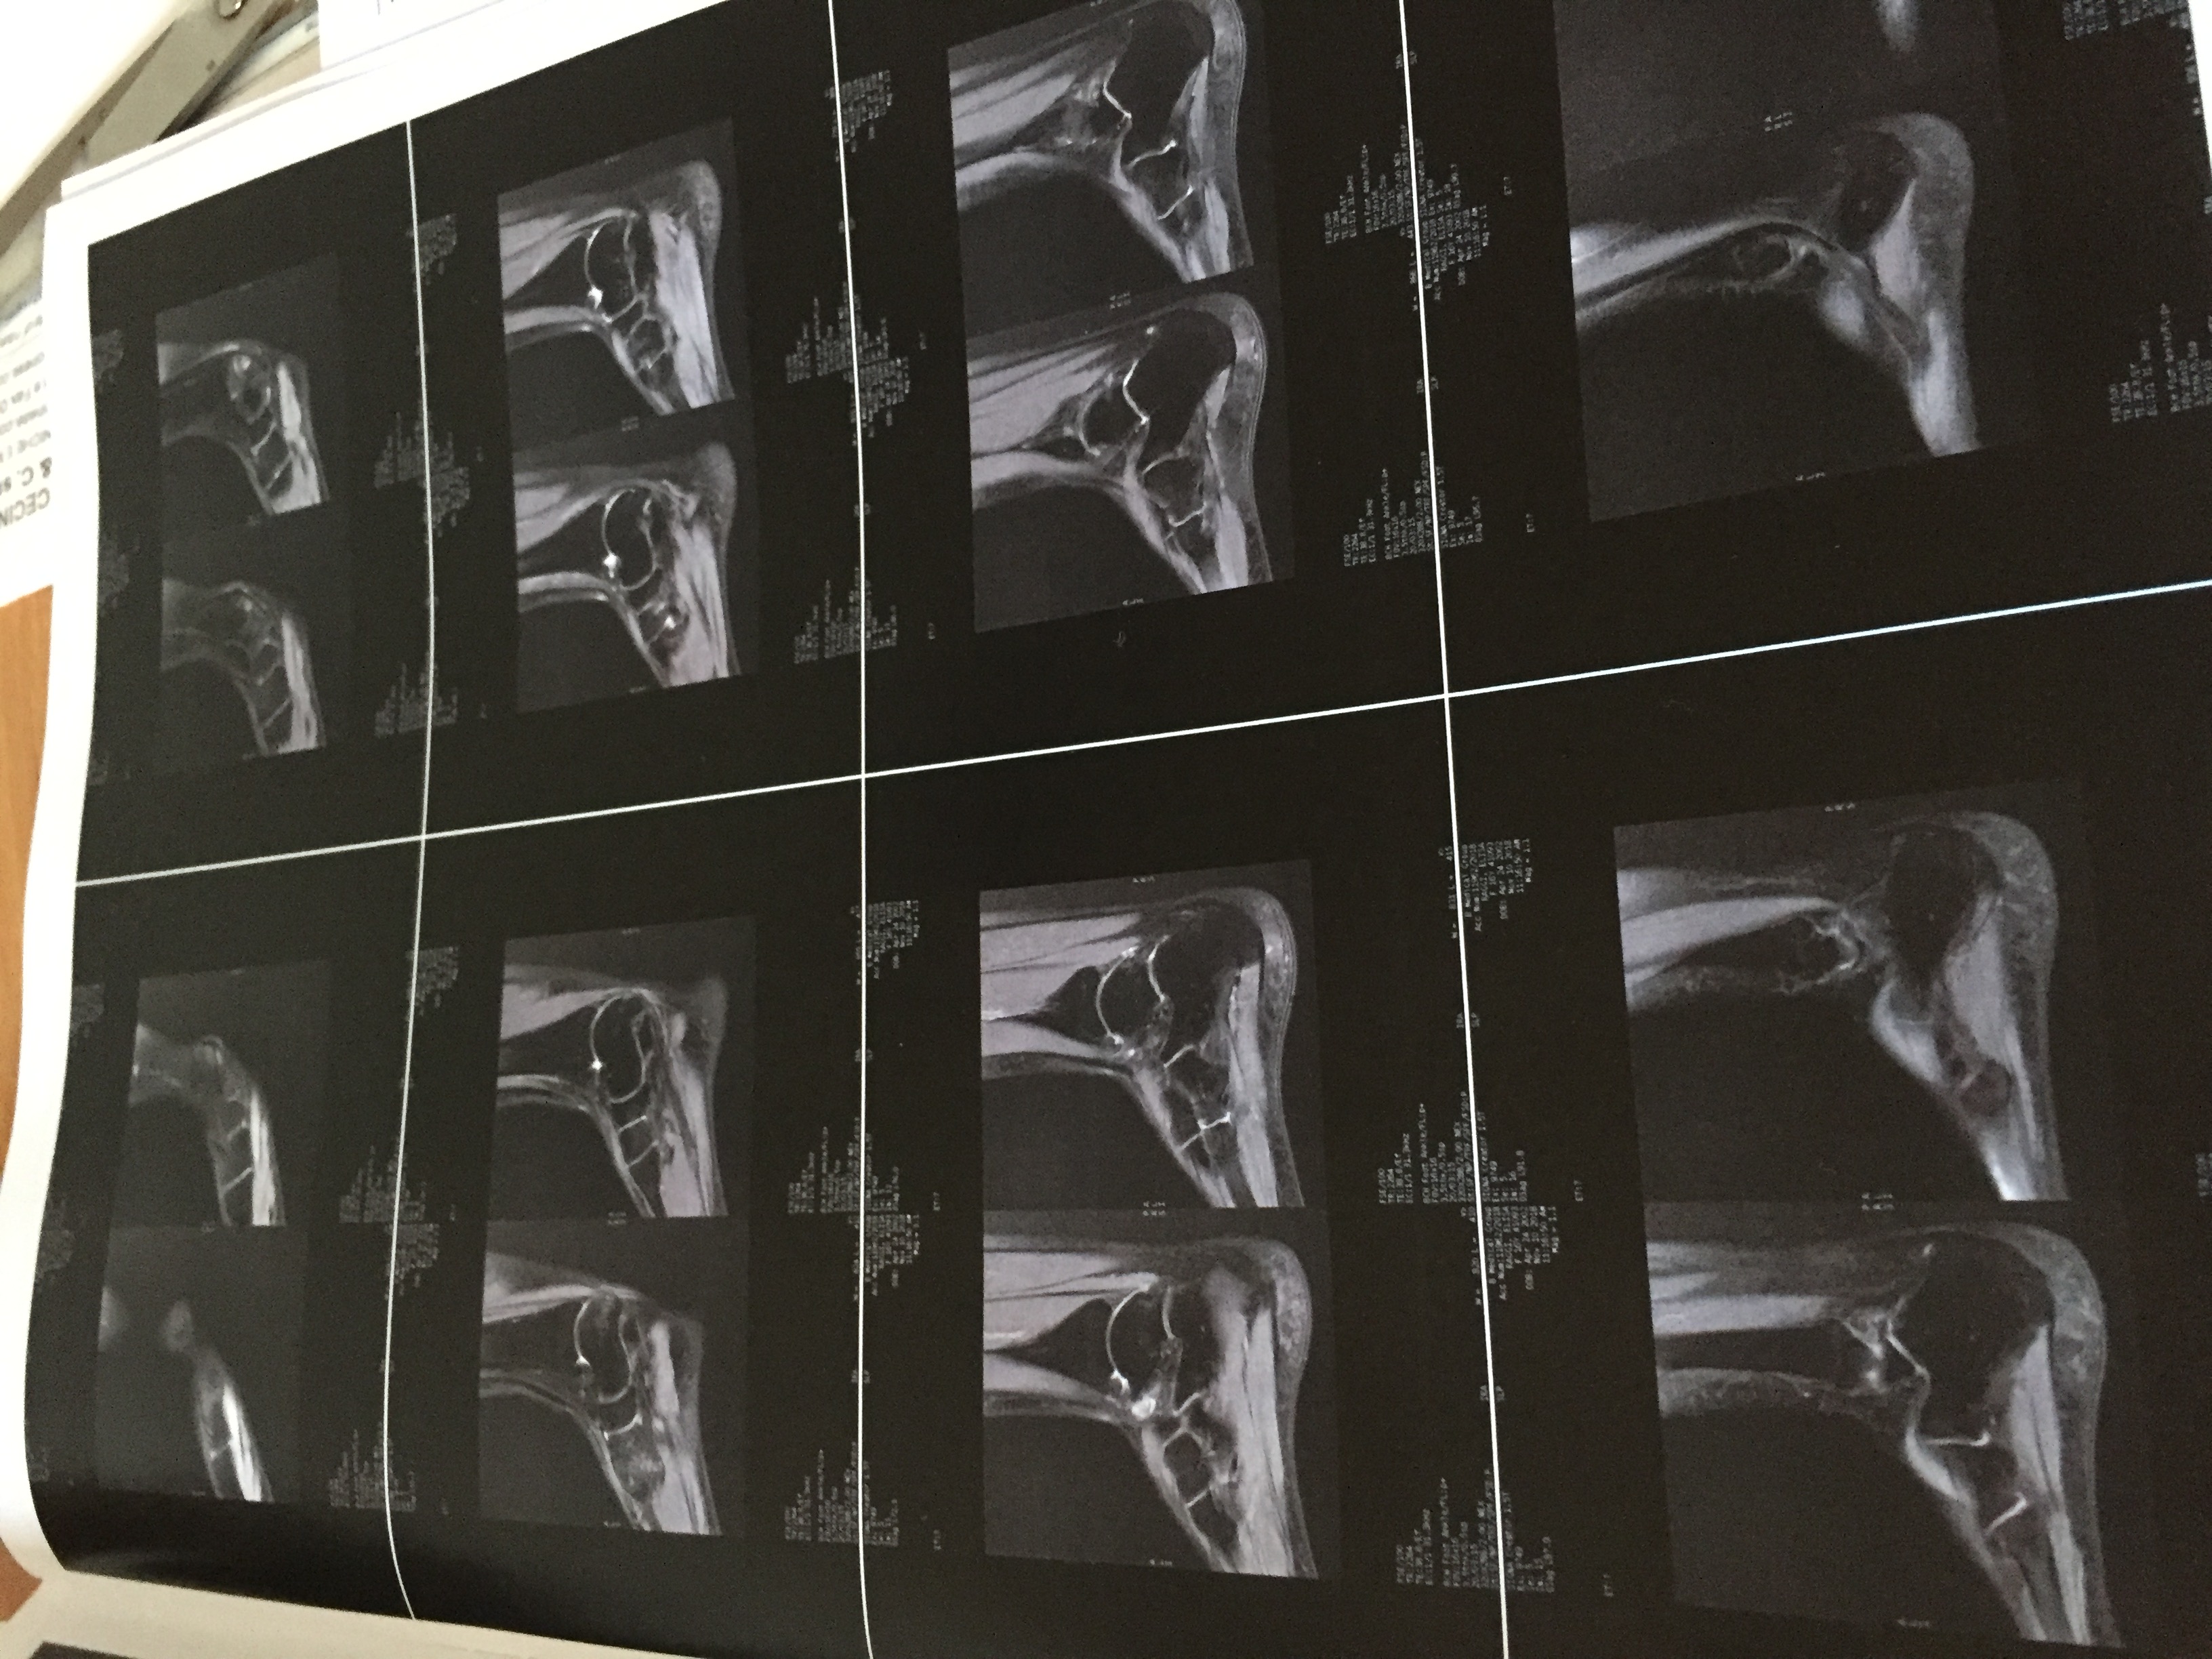

Buongiorno mia figlia ginnasta è circa 1 mese che dolore all collo del piede dopo 17 laserhag poco miglioramento

Le invio delle foto della rm , può darmi informazioni?

7725915C-94CD-4F13-B547-D9E91C258238.jpeg

9D220D31-C5F4-4D53-B313-ACBB0C1CAF8F.jpeg

B69BBB8E-013D-4107-8432-DB1DE06104EF.jpeg